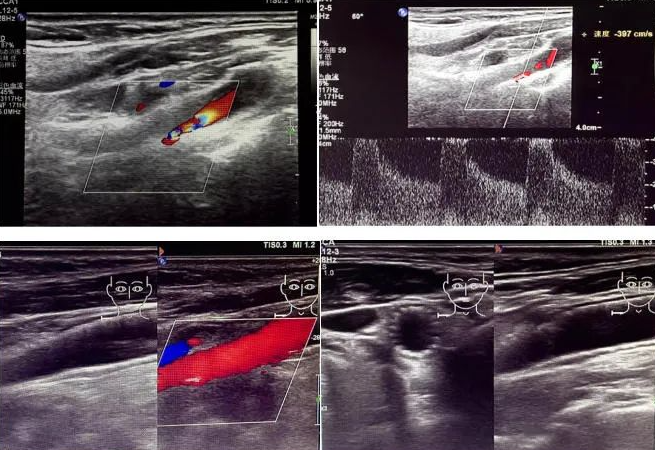

該患者因反復(fù)頭暈前來國文醫(yī)院就診。經(jīng)醫(yī)院超聲科運(yùn)用高端超聲設(shè)備進(jìn)行頸動脈超聲檢查后發(fā)現(xiàn),其右側(cè)頸動脈狹窄程度超過 90%。如此嚴(yán)重的狹窄狀況,猶如高速公路上的嚴(yán)重堵車,使得血液流通受阻,大大增加了腦梗死的風(fēng)險,時刻威脅著患者的生命安全。

頸動脈超聲檢查作為一種無創(chuàng)、安全且準(zhǔn)確的篩查手段,在評估血管健康狀況方面發(fā)揮著重要作用。它能夠清晰地顯示血管的狹窄程度以及斑塊性質(zhì),為臨床診療提供可靠的依據(jù)。國文醫(yī)院超聲科配備的高端超聲設(shè)備,更為精準(zhǔn)診斷提供了有力支持。